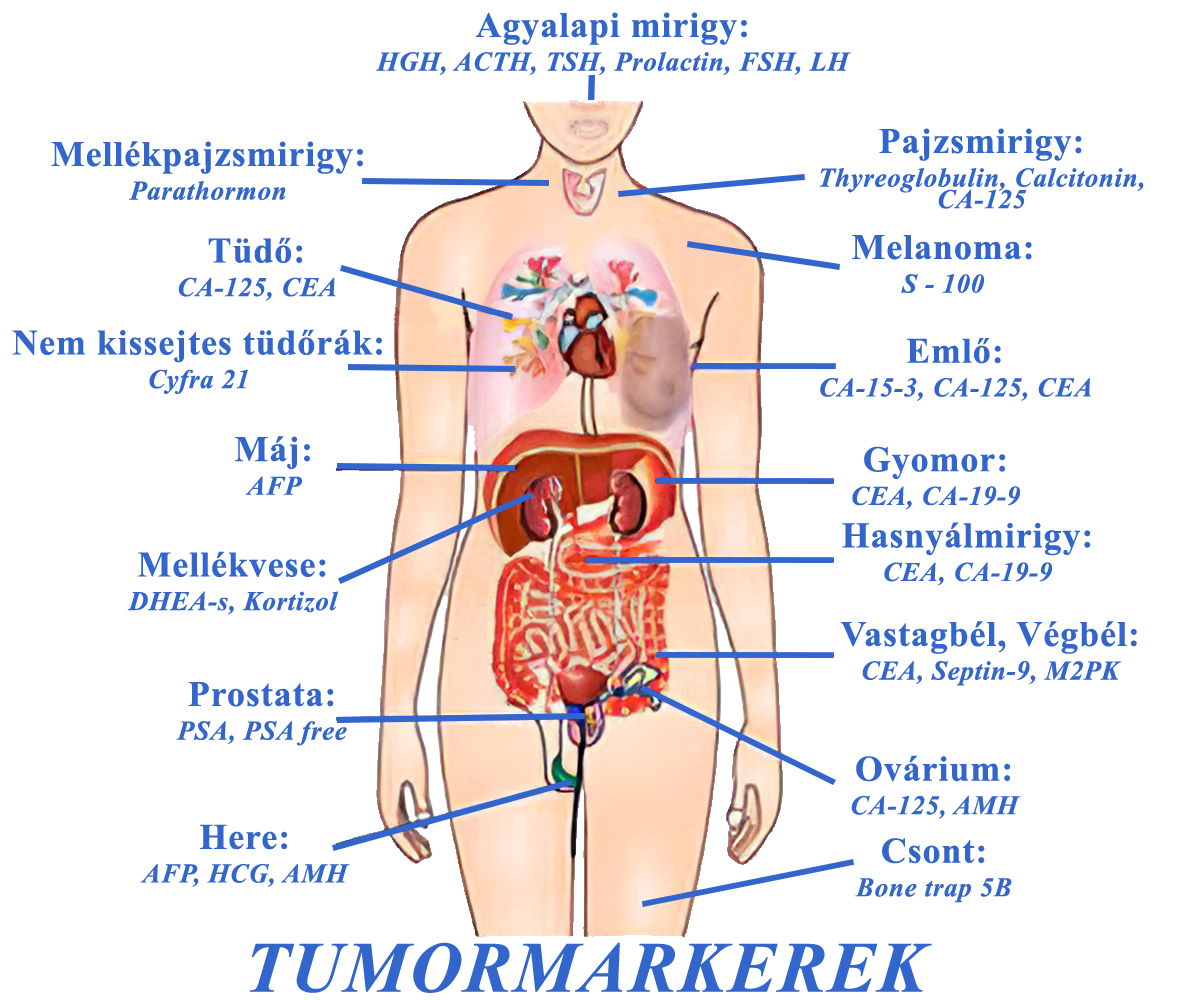

Бесплатное обследование на онкологию: информация и ресурсы